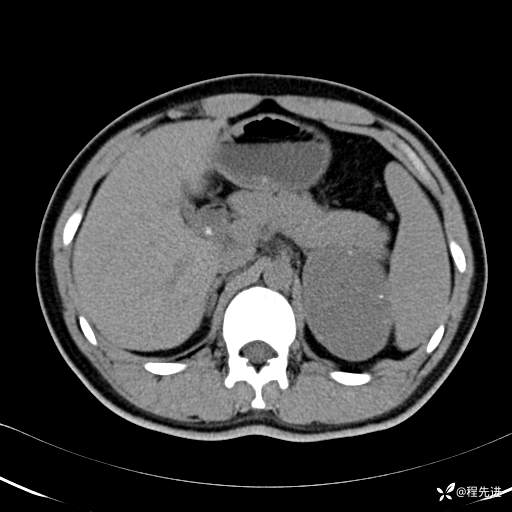

【腹盆】特别精彩病例|体检发现的左侧腹膜后占位期待您的精彩解读

患者年龄:25岁

简要病史:体检发现

CT平扫:(CT值:平扫,27HU,动脉期,27HU,门静脉期,31HU,平衡期,32HU)

CT增强:

平衡期:

冠状位重建: